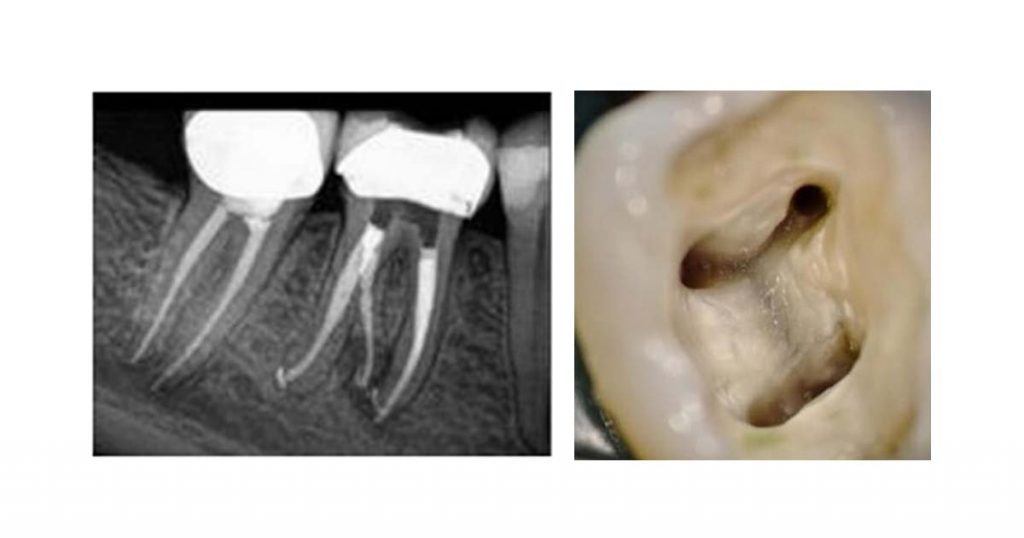

4. Inability to locate extra canals (missed canal orifices):

Failing to locate all canals is one of the primary reasons for endodontic failure. This often arises from insufficient knowledge of canal anatomy, improper access cavity design, or incomplete deroofing of the pulp chamber. Preoperative radiographs help visualize the canals before treatment. Intraoperative radiographs from different angles ensure all canals are identified.